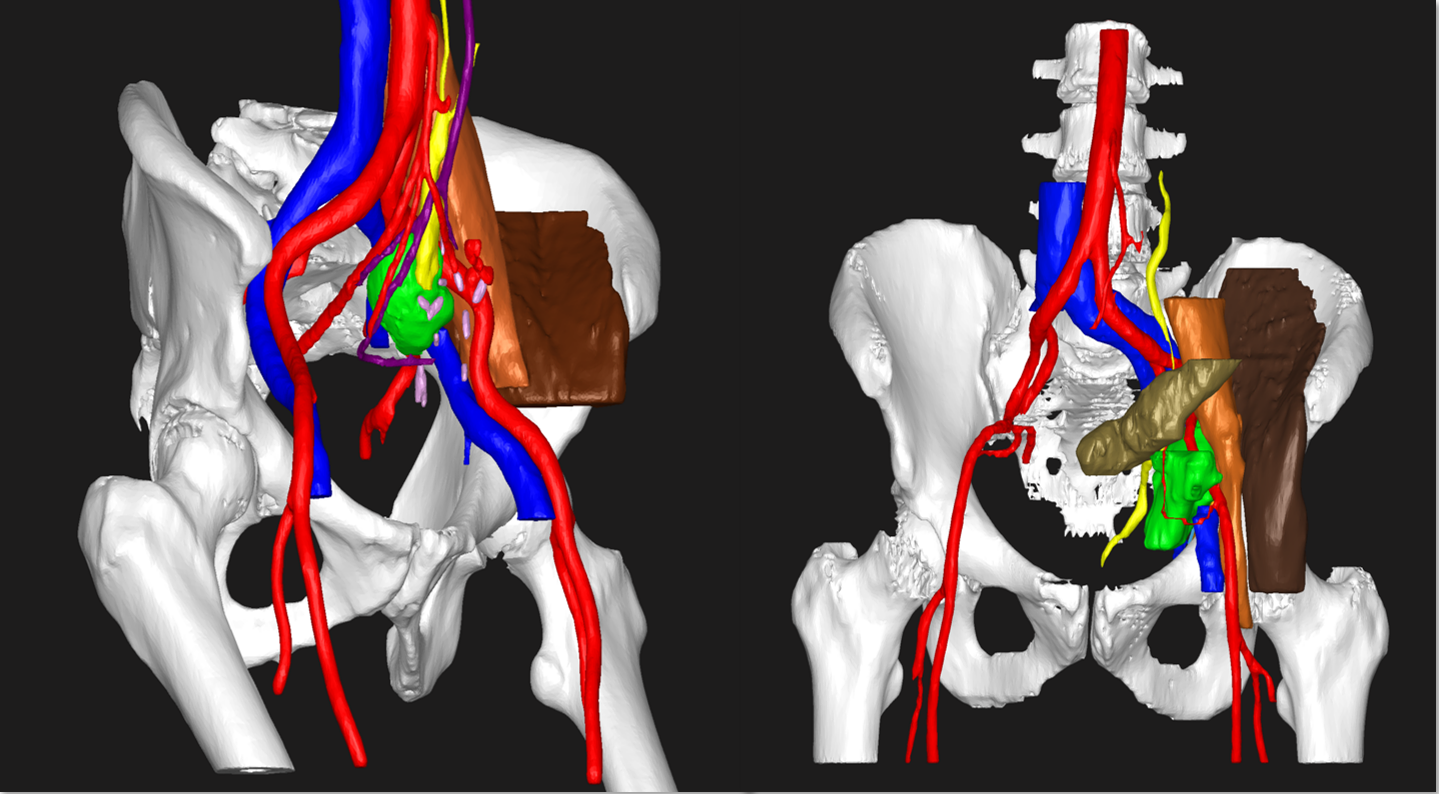

3D Virtual Model for preoperative planning of complex gynecological oncological pathologies